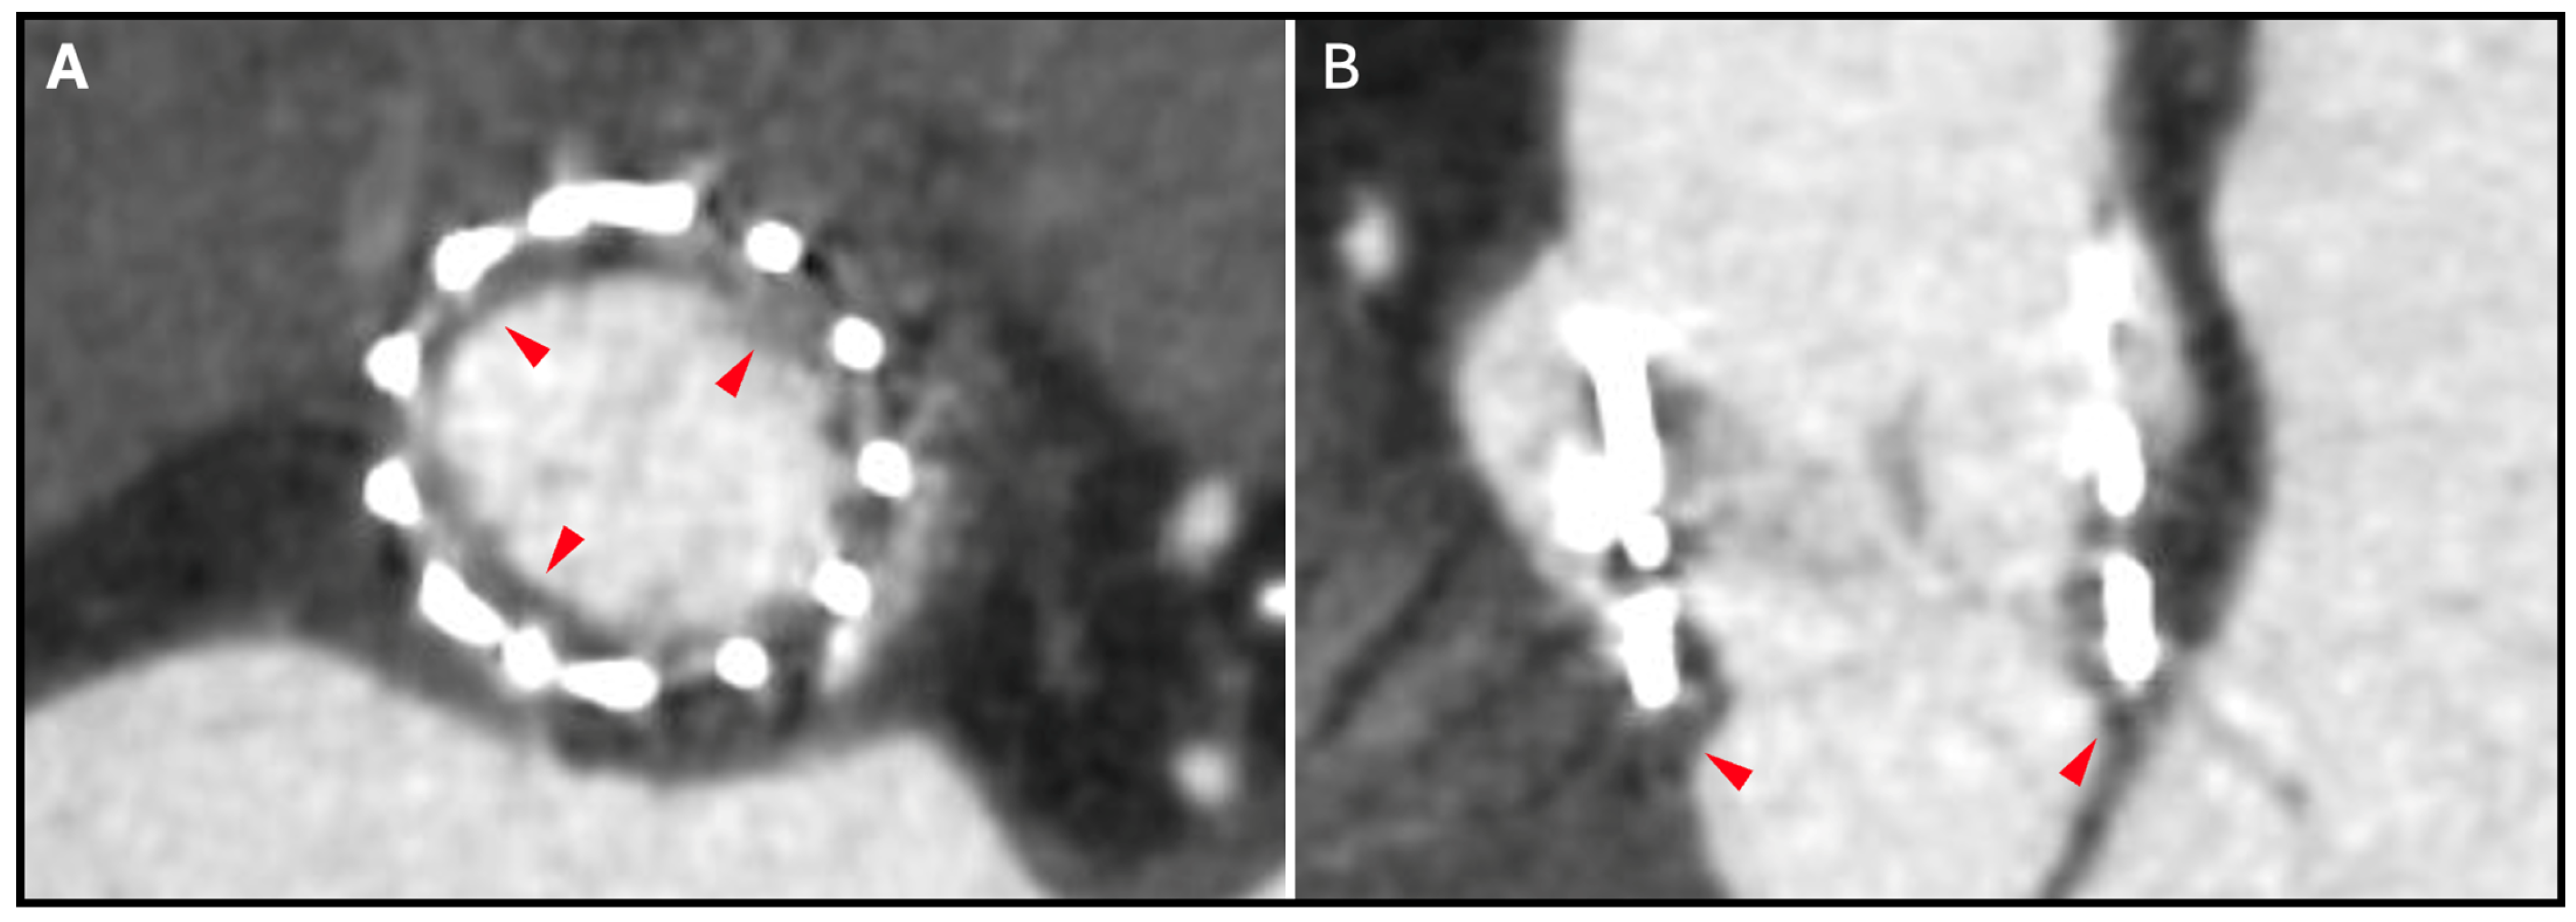

9.2. TAVR in TAVR

13. THV Underexpansion